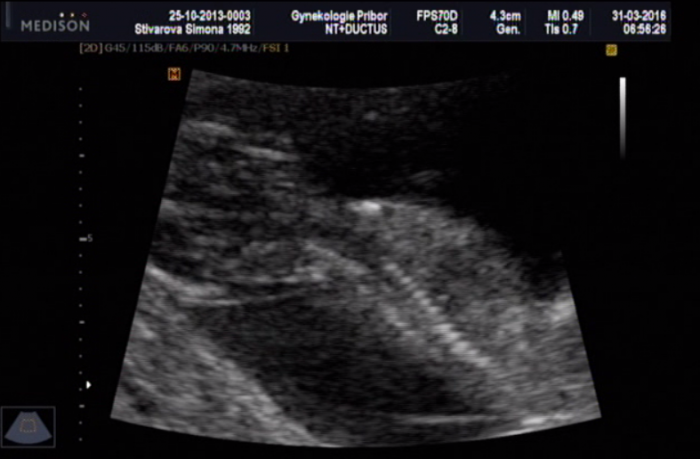

[883491]ja tam teda nevidim vubec nic,ani samotne mimi zda tam teda je vubec zabrane cele

[883496] nee to je jen kousííček právě s pindííkem nejspíše :D mám natočené video tak jsem to pauzla a udělala print screen :)